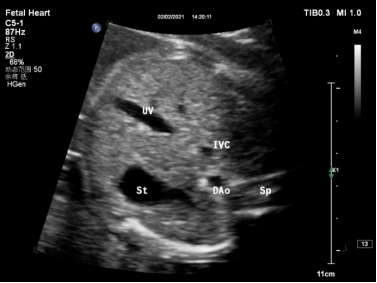

| 显示结构 | 脊柱、胃泡、脐静脉腹内段、下腔静脉、腹主动脉 |

| 观察内容 | 1、2D:腹主动脉位于脊柱的左前方,下腔静脉位于脊柱的右前方,下腔静脉位于腹主动脉的右前方,胃泡位于左上腹腔,正常脐静脉位于腹中略偏左。 |

| 2、CDFI:显示脐静脉与下腔静脉之间的一段明亮血流,即静脉导管。 | |

| (图1、2) | |

| 测量参数 | PW:静脉导管血流频谱(图3)。 |

| 图1 胎儿胃泡水平腹部横切面二维显像 | 图2 胎儿胃泡水平腹部横切面彩色多普勒显像 |

注:UV:脐静脉;St:胃泡;DAo:降主动脉(腹主动脉);Sp:脊柱;IVC:下腔静脉;DV:静脉导管